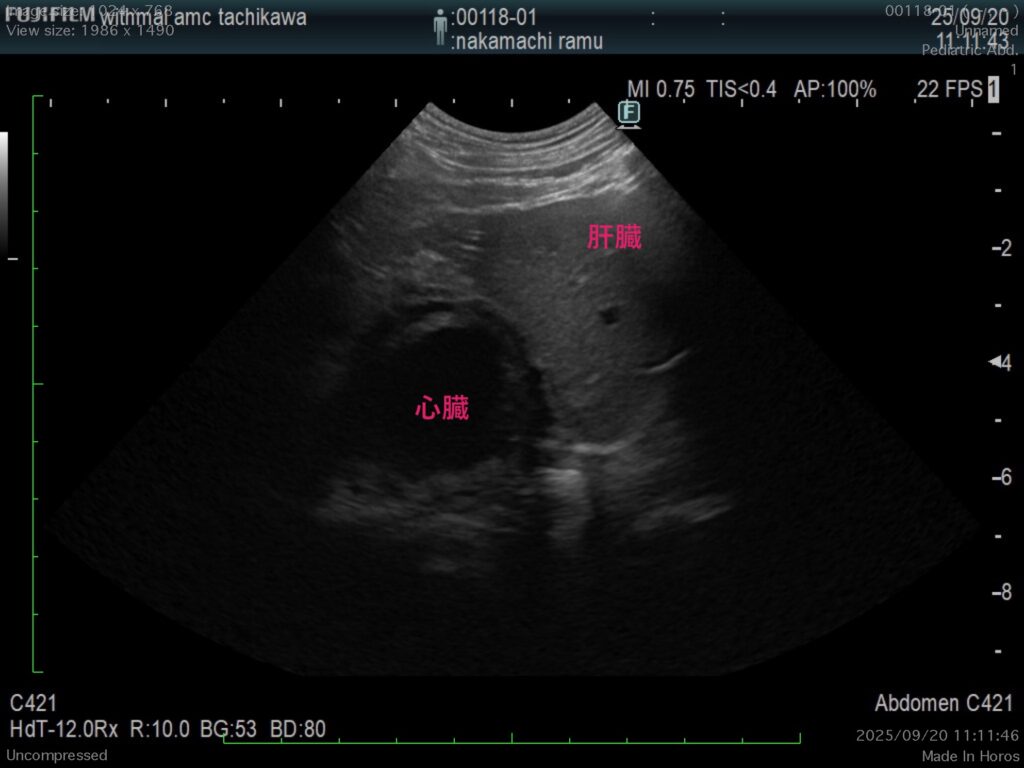

エコー検査、CT検査にて胸腔内(心臓尾側)に肝臓実質(方形葉)が脱出。

・心膜横隔膜ヘルニア